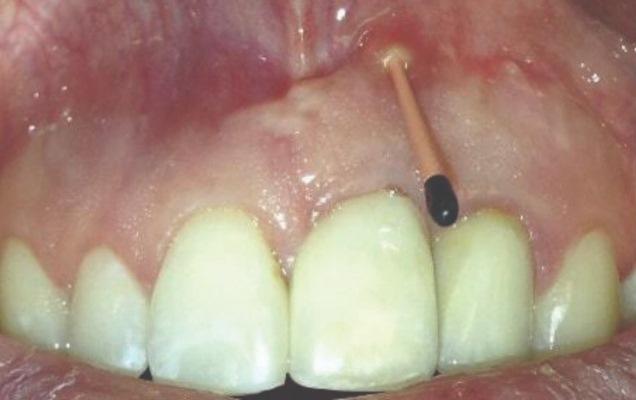

Пациент 2: Здоровый пациент мужского пола 63 лет обратился с имплантатом № 1.3, у которого диагностирован РПИ, на который повлиял ранее эндодонтически леченный и сломанный зуб № 1.4 (Фото 3 и Фото 4). Глубина зондирования вокруг имплантата составляла от 4 до 10 мм (Таблица 1), причем наиболее серьезная потеря кости наблюдалась с дистальной стороны имплантата № 1.3 (Фото 3 и Фото 4).

Фото 3 и Фото 4. Случай 2: Первоначальная клиническая картина, показывающая имплантат № 1.3 с РПИ, на который повлиял сломанный зуб № 1.4 (Фото 3); рентгеновский снимок, показывающий сломанный зуб № 1.4 с периапикальным поражением, распространяющимся на дистальную сторону имплантата № 1.3 (Фото 4).